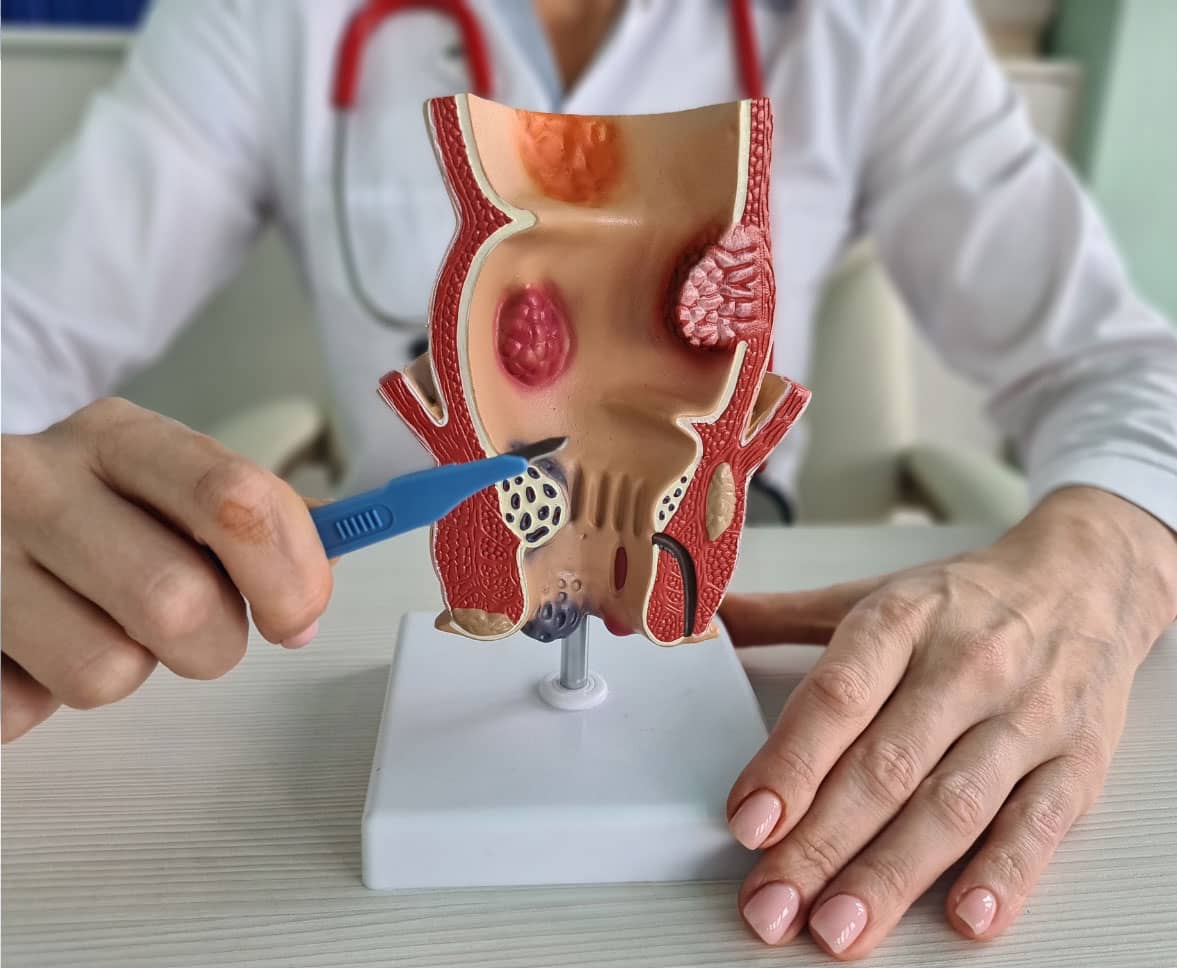

ਬਵਾਸੀਰ (ਹੈਮੋਰਾਇਡਸ) ਗੁਦਾ ਅਤੇ ਮਲਦਵਾਰ ਦੀਆਂ ਸੋਜੀ ਹੋਈਆਂ ਰਗਾਂ ਹਨ। ਅੰਦਰੂਨੀ ਬਵਾਸੀਰ ਨੂੰ 4 ਗਰੇਡਾਂ ’ਚ ਵੰਡਿਆ ਜਾਂਦਾ ਹੈ: